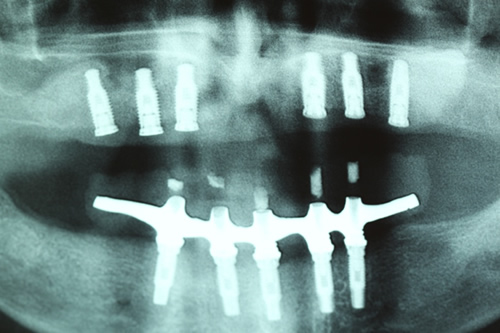

Radiografia 8 meses após do enxerto e 1 dia após implantação

Carregamento com protocolo superior e inferior